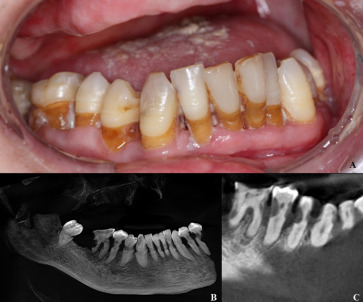

Radiation also directly weakens teeth. Microscopic studies show enamel/dentin become more brittle and demineralize more easily after RT. Odontoblastic damage and pulpal hypovascularity induce subsurface “radiation caries” and collagen breakdown. Clinically, lesions appear rapidly in non‑classic sites: circumferential cervical (“caries circularis”) and incisal/cuspal areas of incisors and molars. These lesions often progress without pain, and can destroy previously healthy teeth within months

Early detection: After RT, patients are followed closely. Surveillance visits are recommended at least every 3–6 months. At each recall, the dentist should inspect all tooth surfaces, use explorers/radiographs to find early lesions, and check for demineralization (often subtle at cervical margins). Fluorescence or digital imaging devices may aid detection of hidden lesions. Frequent monitoring allows intervention on incipient caries (e.g. resin infiltration, silver diamine fluoride, or sealants) before cavitation.